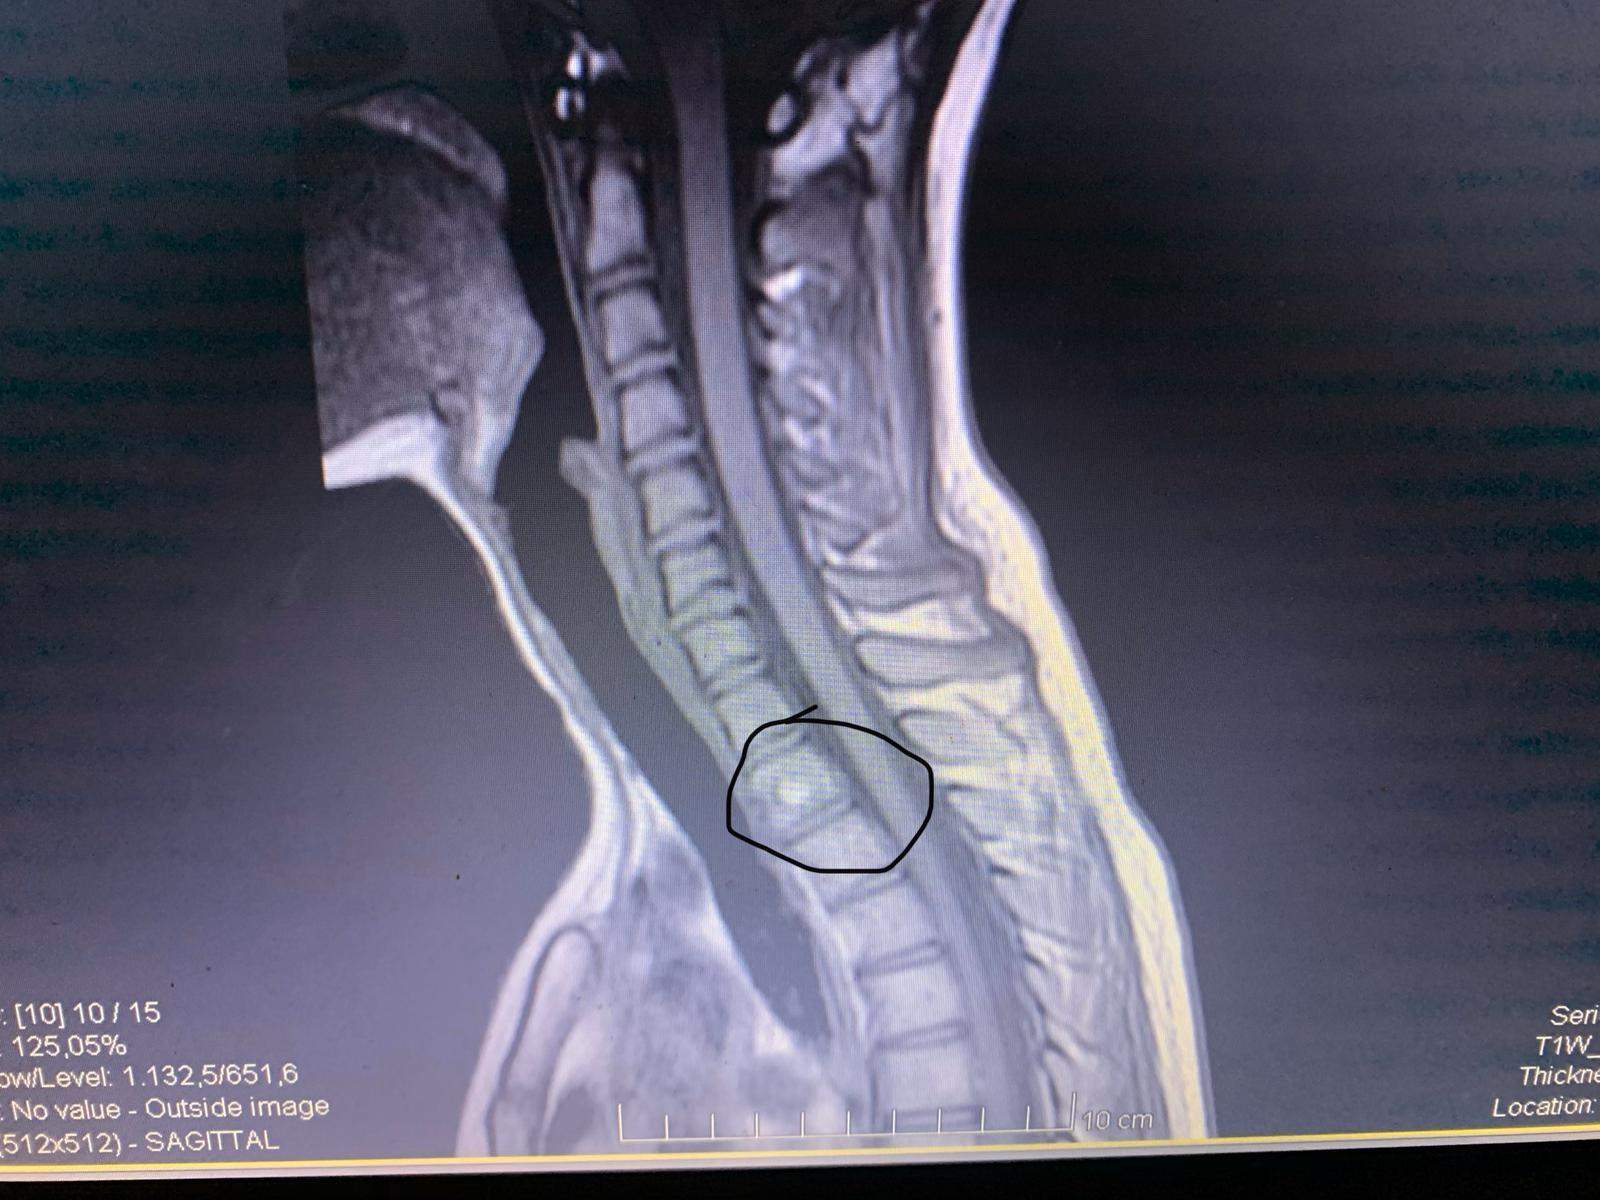

Zwischenwirbelloch.mrt von cervical spine : mäßiger bis schwerer hinterer zentraler bandscheibenvorsprung von c3/4 bis c5/6 bandscheiben mit einer länge von 2,0 cm kleiner posteriorer subligamentöser flüssigkeitssammlung.

Treten Rückenschmerzen oder Nackenschmerzen im Bereich der Halswirbelsäule auf, spricht man von einem HWS- Syndrom oder auch Zervikalsyndrom. Der Patient erhält eine Vollnarkose und liegt auf dem Rücken. Vor allem der mittlere und untere Teil am Übergang zur Brustwirbelsäule können von einem Facettensyndrom betroffen sein. Anatomie der Lendenwirbelsäule auf MR (axial, sagittal und koronalenschnitte) In Deutschland findet nur bei wenigen Indikationen die Erstattung der CT von der Gesetzlichen .Sagittale MRT-Aufnahme der zervikalen Wirbelsäule in T1-Wichtung.

MRT der Wirbelsäule